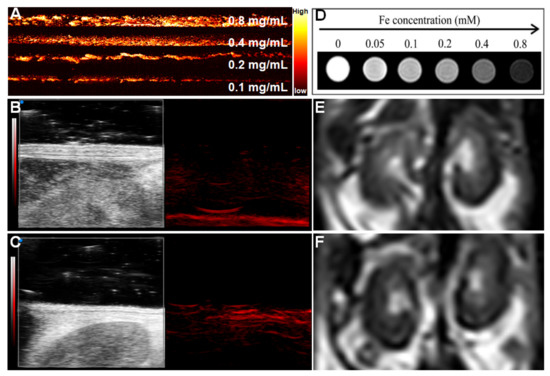

To explore the PA performance of Nec-1/PDA@Pt-Fe3O4, we used a variable wavelength pulsed laser (680–970 nm) and an input laser with a frequency of 30 MHz. The results showed that PDA@Pt-Fe3O4 exhibited extremely strong PA signal intensity, and the intensity of the photoacoustic signal increased with PDA@Pt-Fe3O4 concentration (Figure 3A) possibly because of the PA-enhancing effect of PDA [23]. In addition, the photoacoustic image of mouse kidneys before and after injection of 100 μL Nec-1/PDA@Pt-Fe3O4 at a concentration of 1 mg/mL was investigated. The results are shown in Figure 3B,C. After the injection of nanoprobes, the photoacoustic signal of blood vessels in the renal region was significantly enhanced, and the renal contour became clear, indicating that Nec-1/PDA@Pt-Fe3O4 had an excellent performance in PA images.

The MRI performance of Nec-1/PDA@Pt-Fe3O4 was investigated with 3.0T MRI. The detailed parameters are shown in the Methods section. As shown in Figure 3D, the T2-weighted signal intensity decreased gradually with increasing concentration. We also investigated MRI performance in vivo. As shown in Figure 3E,F, after Nec-1/PDA@Pt-Fe3O4 was injected into the mice in vivo, the T2-weighted signal was negatively enhanced.

The above results showed that Nec-1/PDA@Pt-Fe3O4 is an outstanding PA/MR dual-mode imaging agent.

Figure 3. Photoacoustic/magnetic resonance dual-mode imaging. (A) Photoacoustic imaging at different concentrations of Nec-1/PDA@Pt-Fe3O4 in vitro, Photoacoustic imaging of mice kidney before (B) and after (C) adding 1mg/mL Nec-1/PDA@Pt-Fe3O4 in vivo. (D) T2-weighted magnetic resonance imaging in vitro at different concentrations of Nec-1/PDA@Pt-Fe3O4. Magnetic resonance imaging of mice kidneys before (E) and after (F) adding Nec-1/PDA@Pt-Fe3O4 in vivo.